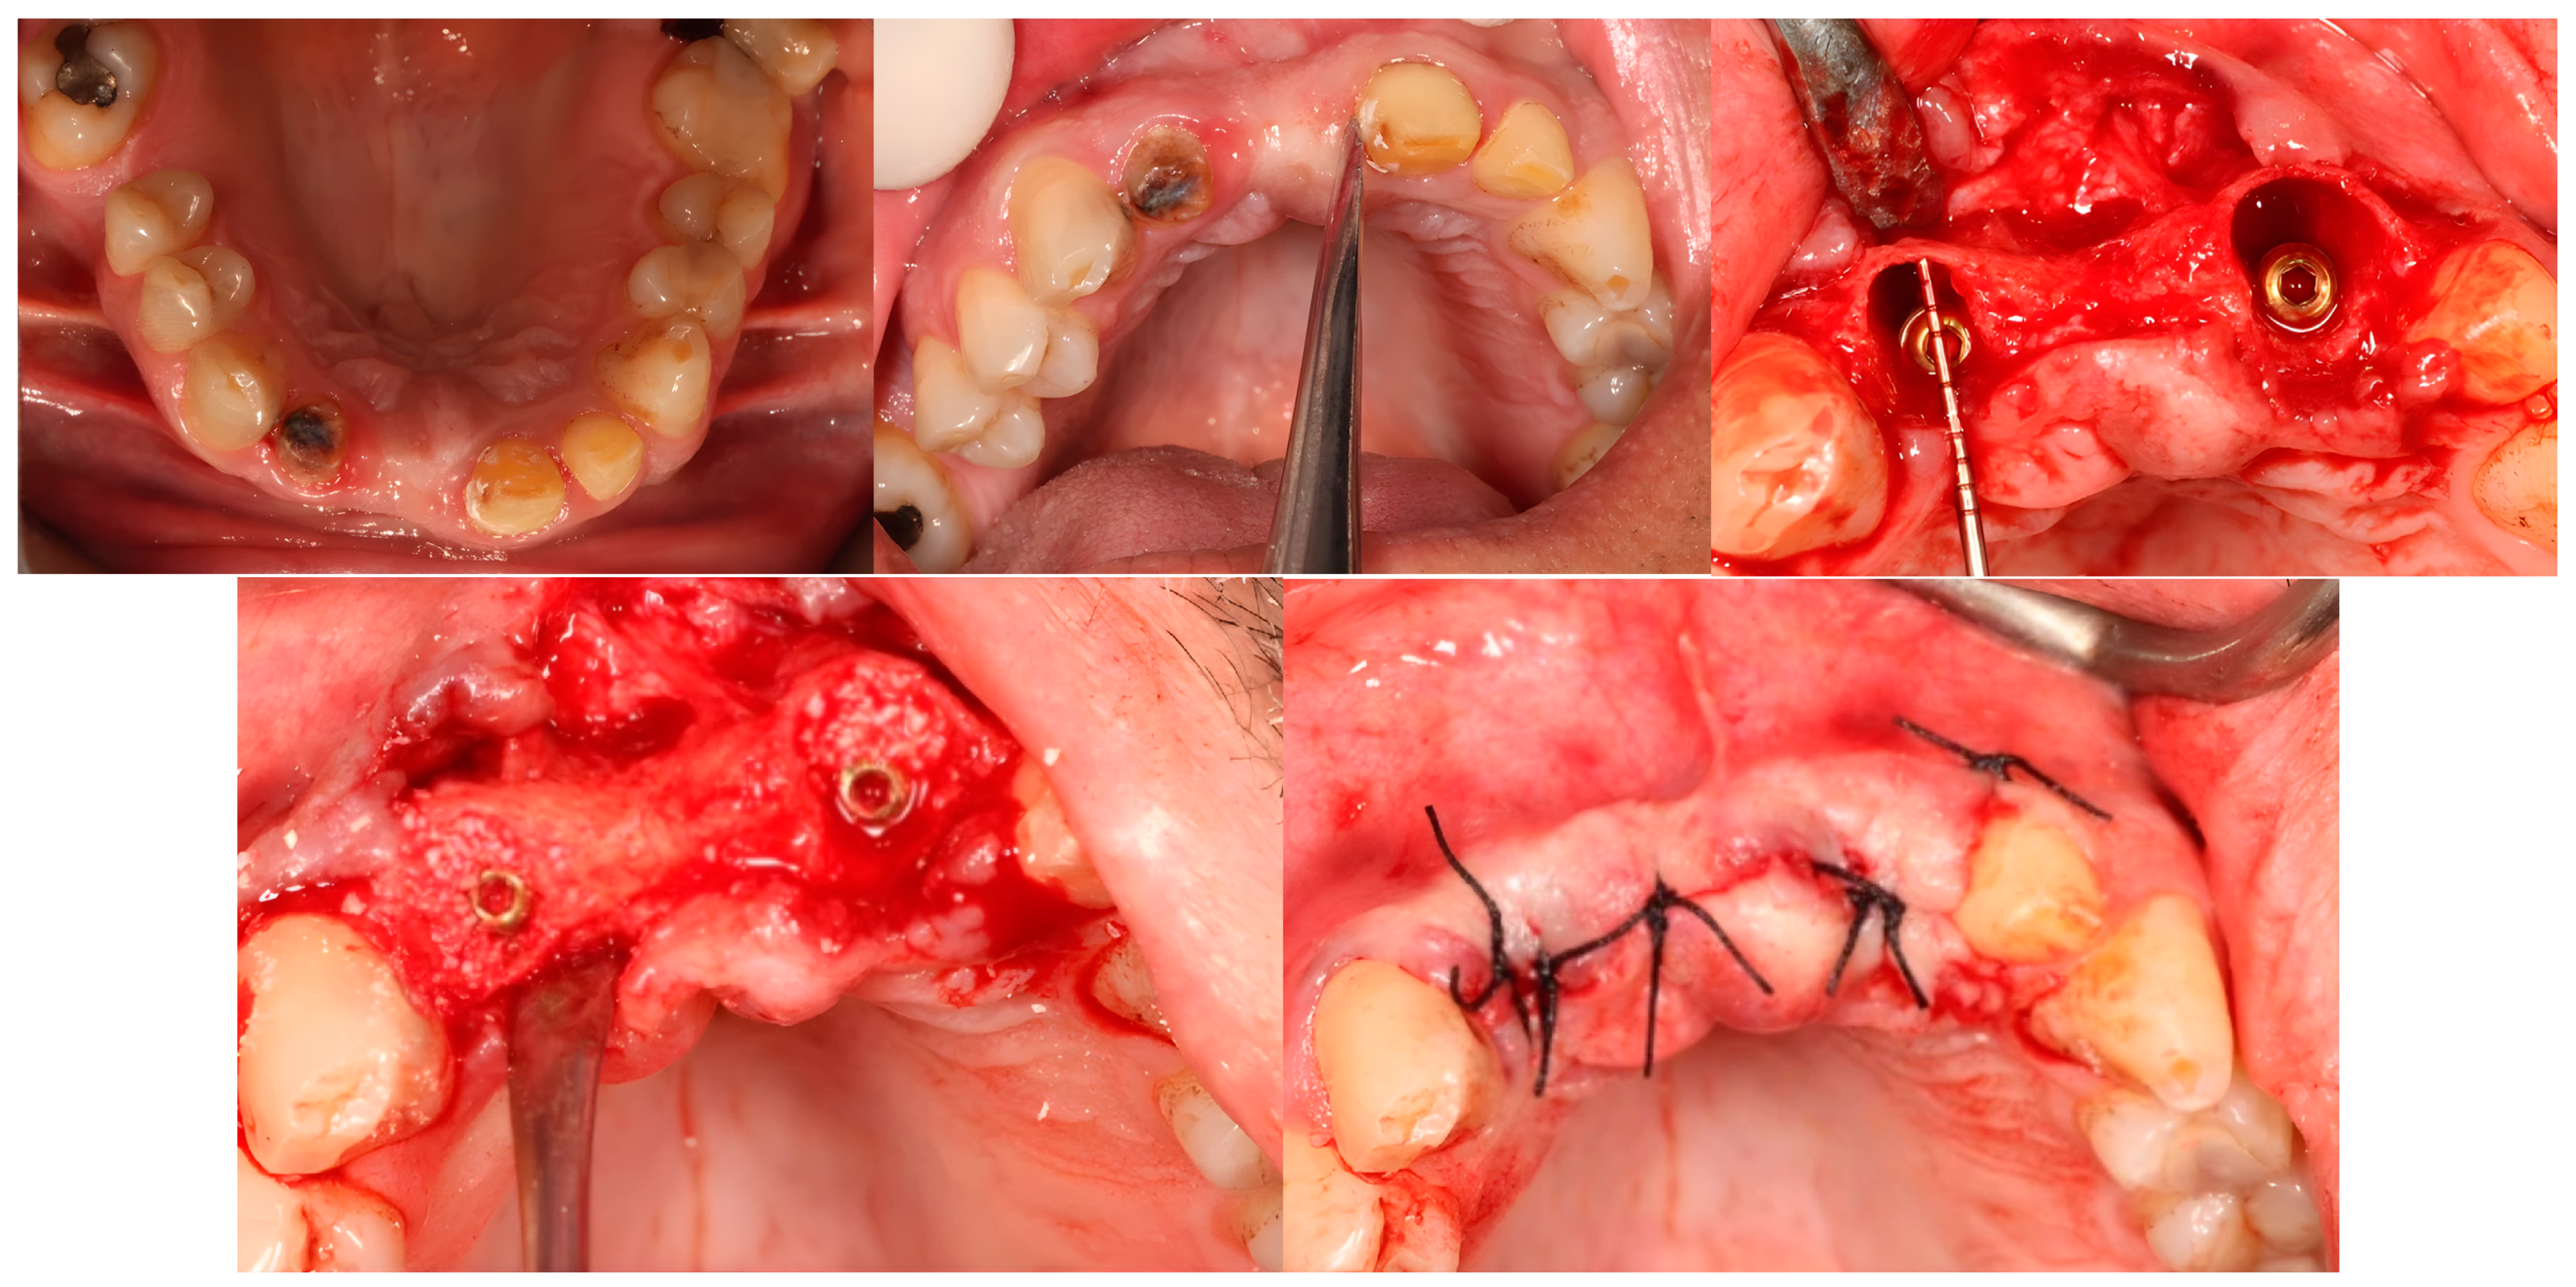

As the indicated number of implants were inserted, the gaps were filled with either the AMDG or Bio-Oss® graft and then the flap was closed using a 3/0 silk suture (Silk, Dogsan, Istanbul, Türkiye) (Figure 2). The patients were kept on oral antibiotics (Augmentin-Bid, Glaxosmithkline, Istanbul, Türkiye), analgesics (Arveles, Ufsa, Istanbul, Türkiye), and mouthwash (Chlorobenzyl, Drogsan, Ankara, Türkiye) for 7 days. Ten days later, the sutures were removed. A clinical follow-up examination was conducted once a month, reminding the patients of the necessity of oral hygiene and to keep it maintained.

Figure 2. Immediate implantation and horizontal gap augmentation.